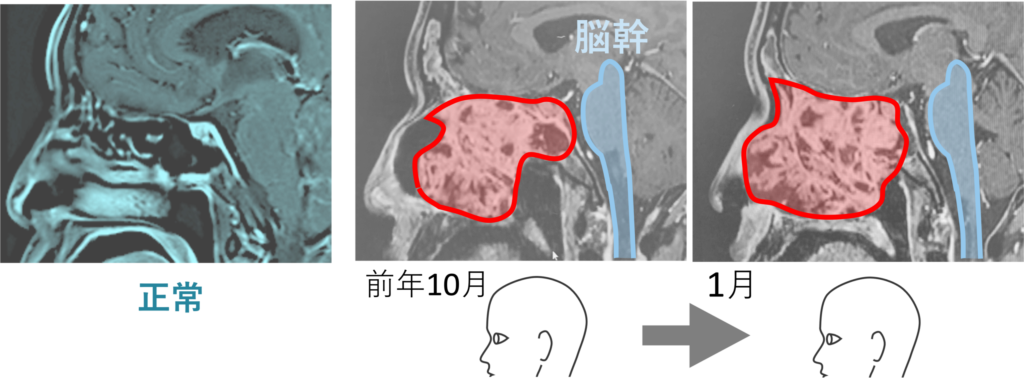

前年10月の画像を見ると、ガンの向かって左 (鼻のあたり) に空洞があることが分かる。まだガンが大きくなるスペースは残されていた。ところが1月の画像をみるとその空洞はなくなっている。もうガンが大きくなるスペースがなくなり、すし詰め状態となっている。こうなると、やがて脳幹 (画像の青色でなぞった部分) をガンが襲うことになる。これは死を意味する。後述するが、ドクターが予測した その時“” は、3月中であった。10月から1月にかけての巨大化の速度から、この調子で行くと3月に脳幹に達すると推測したのだ。

ガンの大きさはほぼ変わっていない。おそらくだが、ドクターは怪訝な思いであっただろう。3月にXデーは来ると予測したにも関わらず、進行が止まったのである。これは初診の血塊排出が大きく関わると見る。

いやよく見ると、わずかだが大きくなったようにも見える。下段で後述するが、このときすでにガン中心部の軟化は始まっていたと見る。見た目の画像では変化はないが、「かたい餅」から「やわらかい餅」へと変わり始めていたのである。やや大きくなって見えるのは、ガン自体が「ふやけてきた」のである。ふやけると、当たり前だが大きくなる。そして、それは悪いことではない。カチカチのままでは体外に排出できないからである。